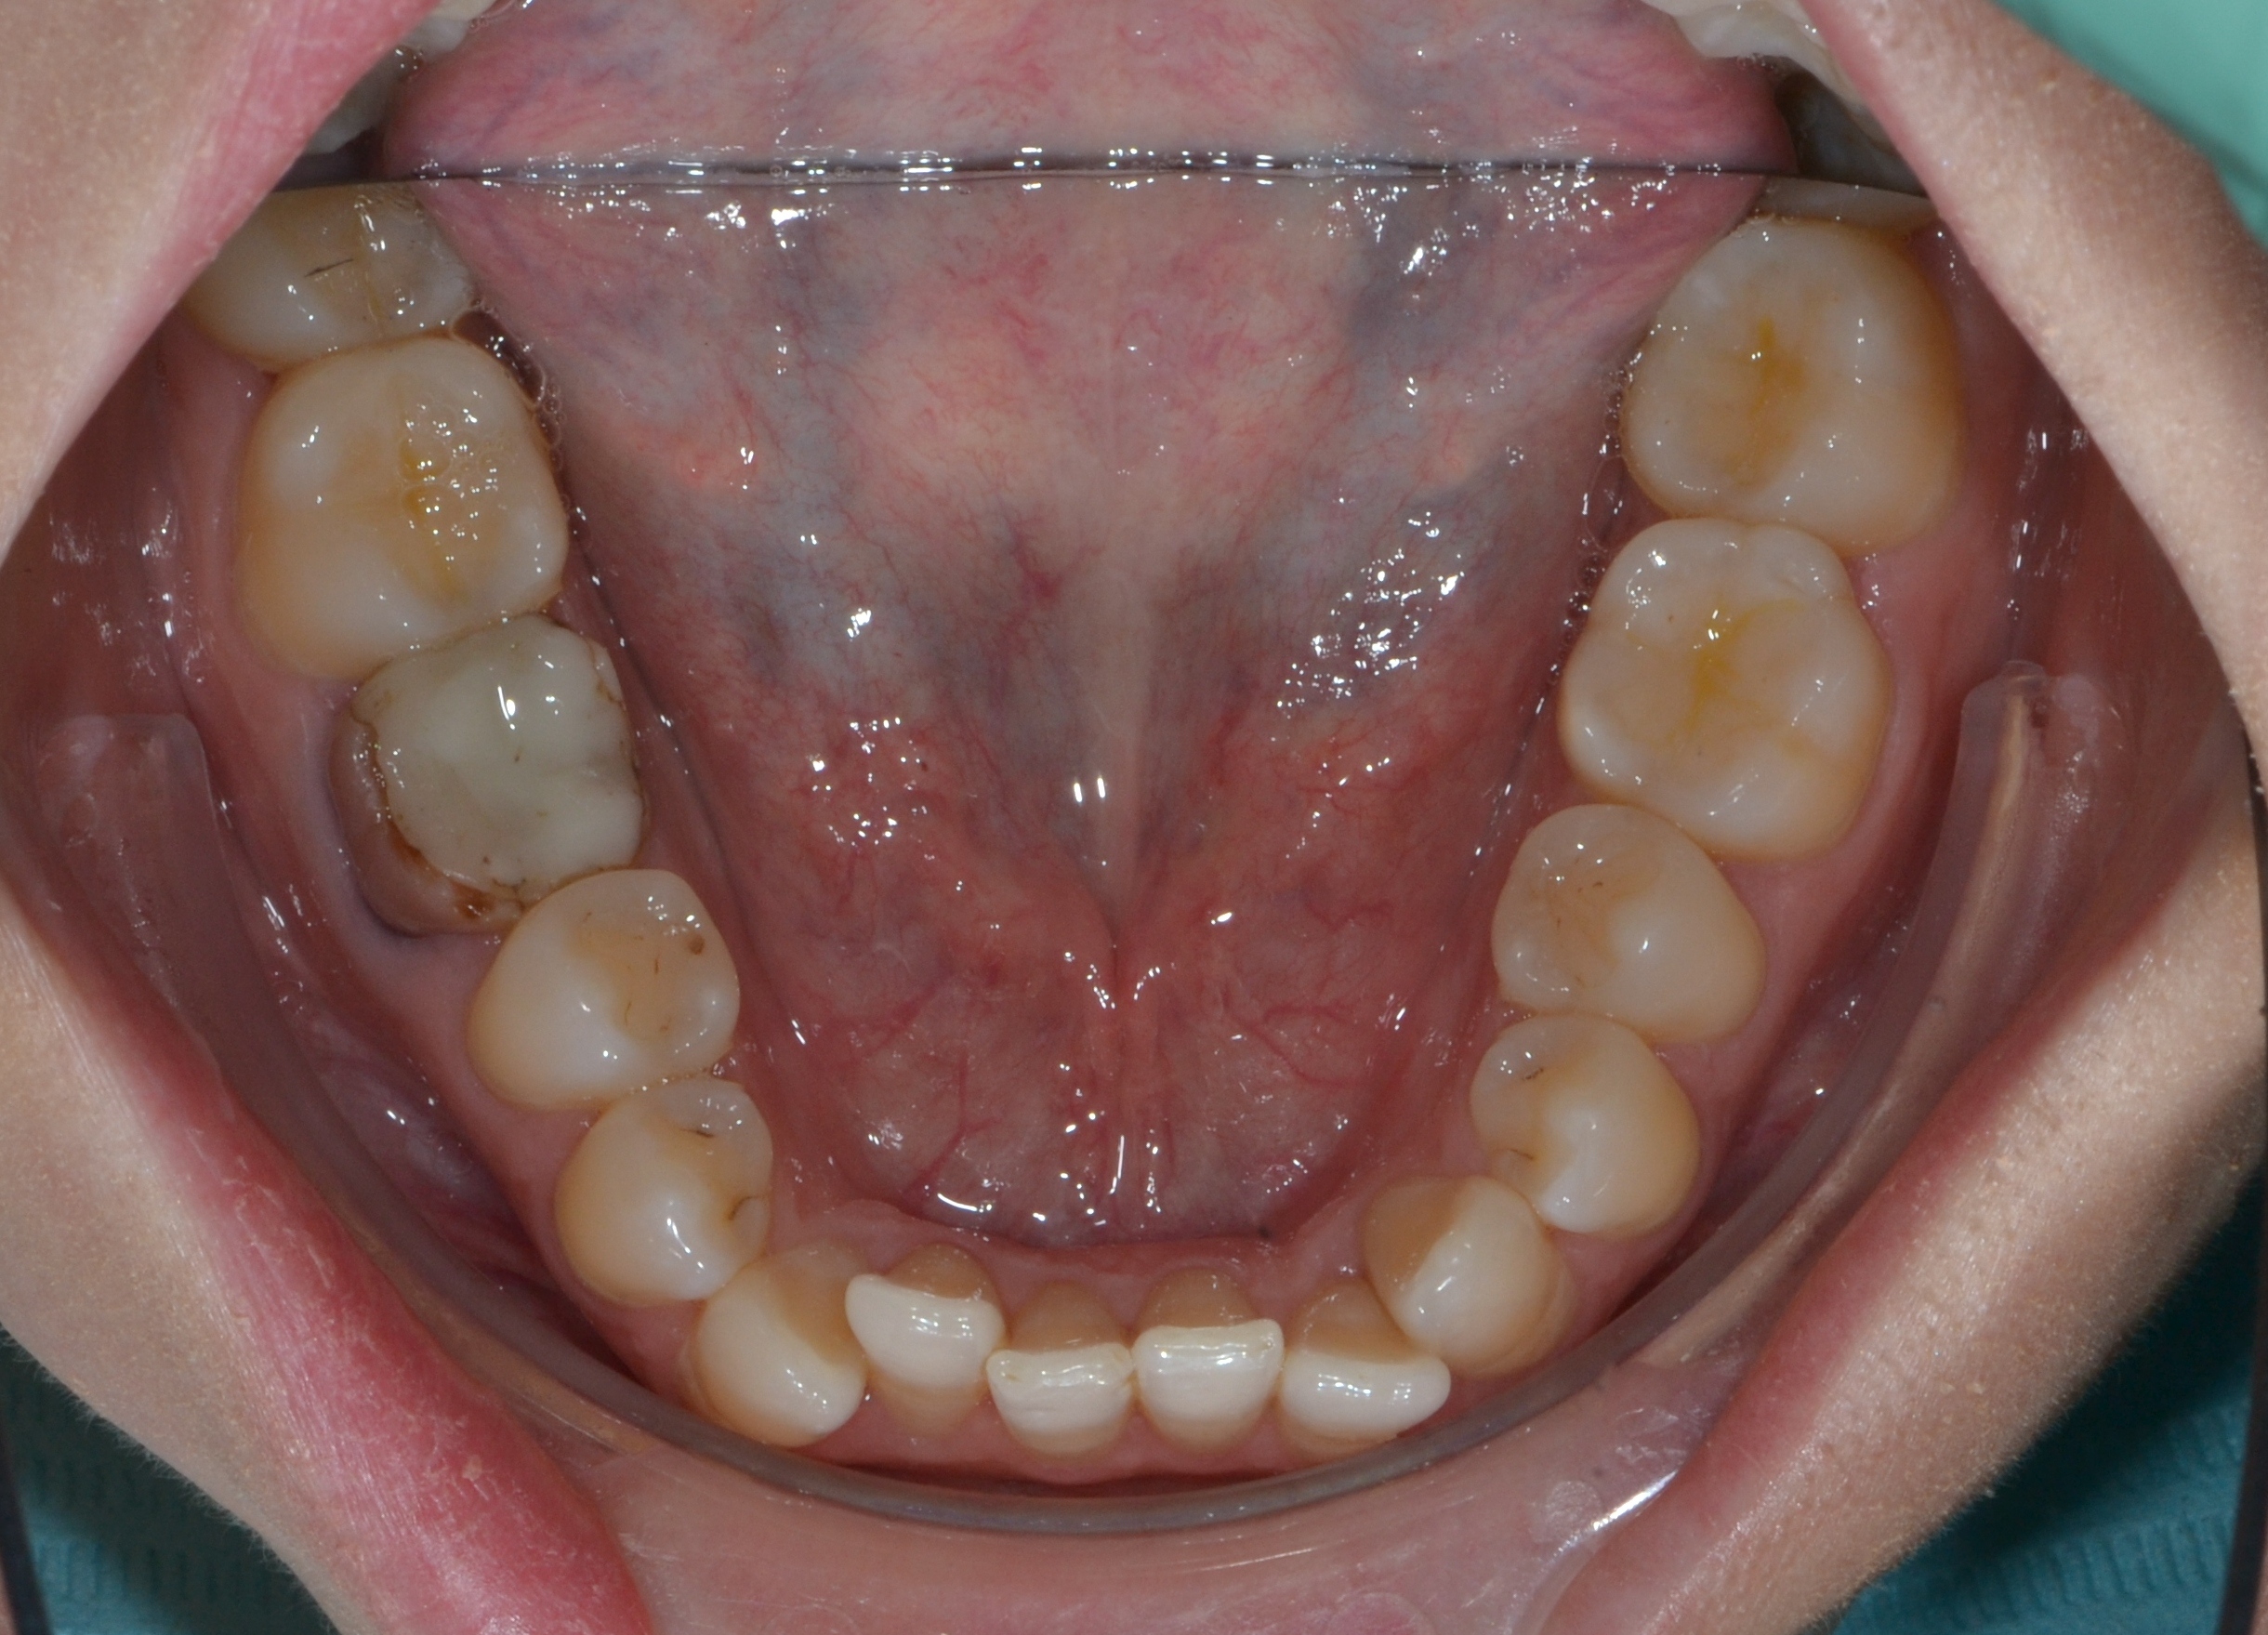

Выявленные проблемы

• Сужение верхнего зубного ряда, сужение и уплощение нижнего

• Глубокий прикус

• Скученное положение 42-32, 12-22

• Дефицит места постоянным зубам

Брекет-система Ultra